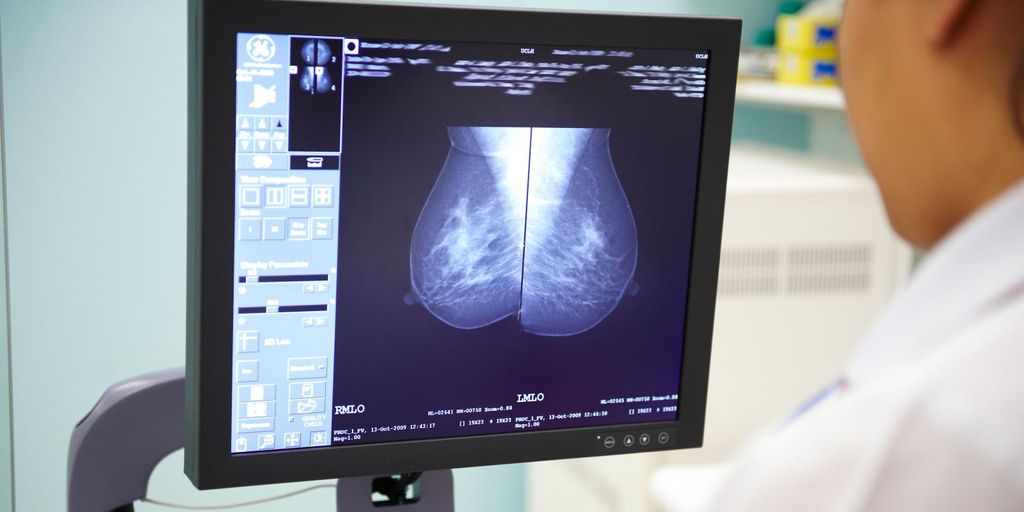

C'è una start up torinese in prima fila nella lotta contro il cancro al seno. Si tratta della Health Triage, che ha appena annunciato un accordo di collaborazione con Cancer Research Horizons e Royal Surrey NHS Foundation Trust. L'azienda nata all'ombra della Mole è specializzata nell'uso dell'intelligenza artificiale per la diagnostica medica e intende promuovere lo screening del cancro al seno, utilizzando i dati di Optimam Medical Image Database.

Nell'ambito della collaborazione, Health Triage utilizzerà i dati Optimam per addestrare modelli di deep learning che identificheranno automaticamente le mammografie senza segni di cancro. Questa scrematura delle mammografie con alta probabilità di negatività ridurrà il carico di lavoro dei radiologi, consentendo loro di concentrarsi inizialmente sui casi sospetti e ad alto rischio.

Dato che circa il 99,1% delle mammografie di screening nel Regno Unito restituiscono un risultato negativo e considerando la carenza di radiologi in molti Paesi, l'uso di soluzioni basate sull'IA ha il potenziale di ridurre l'uso delle risorse sanitarie e ottimizzare i flussi di lavoro in radiologia, mantenendo al contempo i tassi di rilevamento del cancro al seno.

Optimam è un database centralizzato in continua espansione che contiene circa 7 milioni di immagini mammografiche anonimizzate provenienti da oltre 465.000 clienti, raccolte da diversi centri di screening mammografico del Sistema Sanitario Nazionale (National Health System – NHS) del Regno Unito. Il database OPTIMAM e la raccolta continua delle immagini sono gestiti dal Royal Surrey, con il finanziamento continuo di Cancer Research UK. Per garantire la validazione clinica della soluzione di Health Triage, il Gruppo Italiano Screening Mammografico (GISMa) agirà come ente indipendente responsabile della supervisione scientifica del progetto.